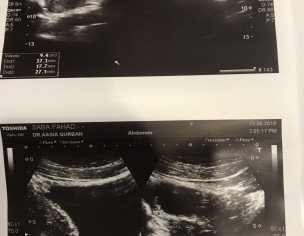

I am trying to conceive since 2 years. Doc told me that i have cysts but one doc said no cysts. Please see this ultrasound report and tell if i have cysts. Also please guide can I conceive with cysts?

You have cystic ovaries.

the pics r nt clear-anyways u shud take second opinion-as u r nt even clear about the status of ur cyst-for e.g. size, no etc...